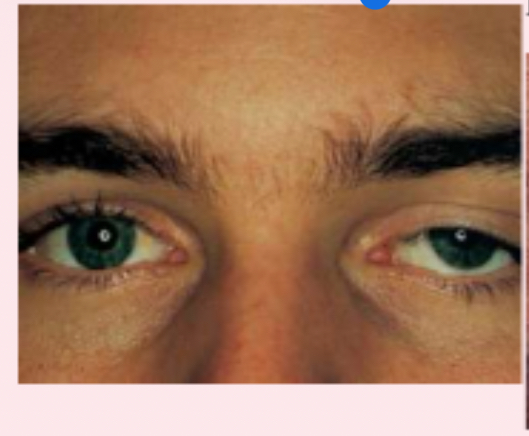

exophthalmos

protruding eyeballs and retracted eyelids